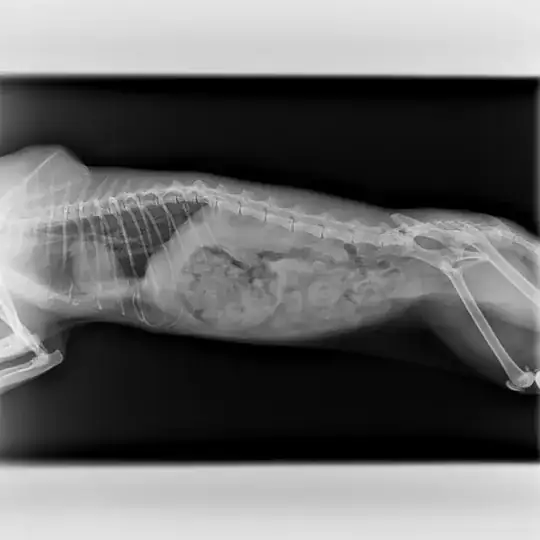

Beside that, we went to a vet to check this cat, blood test, temp., x-ray... so after taking x-ray we saw that her ribs have a strange shape. Local vet says that it seems that this cat suffered possible impact in that area, but he is not sure.

My question is; is it possible that x-ray is mistaken, because of a sudden movement?

Also second x-ray in different cat position shows different shape of ribs.

Can anyone explain, how can I interpret it?